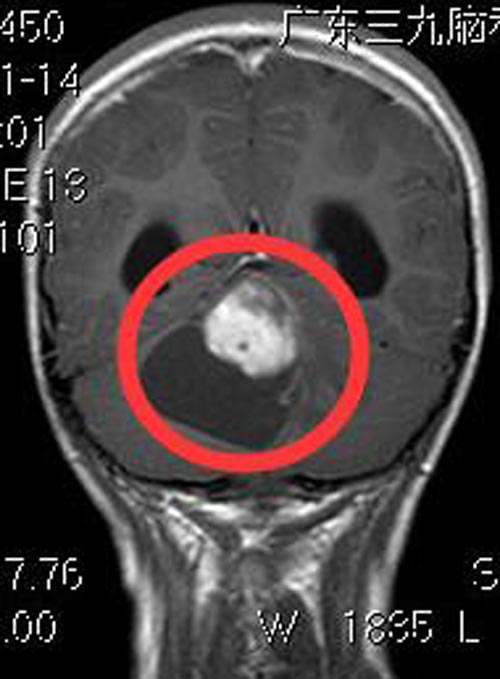

广东三九脑科医院进一步头颅MR检查提示:右侧小脑半球占位性病变,大小约6.1cm×5.4cm×5.2cm,考虑毛细胞型星形细胞瘤可能;幕上梗阻性脑积水(中度),小脑扁桃体下疝,延髓背侧轻微受压。